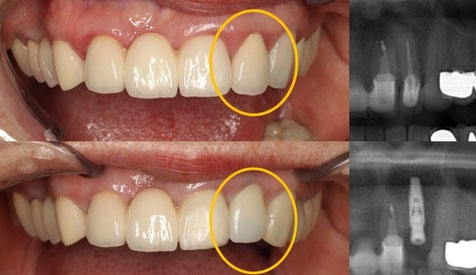

ジルコニア 症例    99000円

インプラント

歯の無い場所の骨に人口の歯を入れます